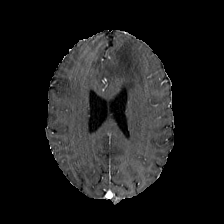

Diffusion models have shown impressive performance for generative modelling of images. In this paper, we present a novel semantic segmentation method based on diffusion models. By modifying the training and sampling scheme, we show that diffusion models can perform lesion segmentation of medical images. To generate an image specific segmentation, we train the model on the ground truth segmentation, and use the image as a prior during training and in every step during the sampling process. With the given stochastic sampling process, we can generate a distribution of segmentation masks. This property allows us to compute pixel-wise uncertainty maps of the segmentation, and allows an implicit ensemble of segmentations that increases the segmentation performance. We evaluate our method on the BRATS2020 dataset for brain tumor segmentation. Compared to state-of-the-art segmentation models, our approach yields good segmentation results and, additionally, detailed uncertainty maps.